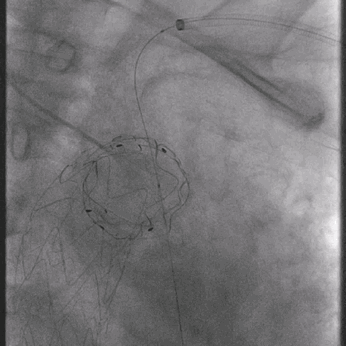

02. 交换0.035"Lunderquist超硬导丝至升主动脉,于左侧颈总动脉开口远端精确定位并释放华脉泰科PTBS3632180覆膜支架。

泥鳅导丝怎么用曲乐丰教授团队:0.018"和0.035"普通泥鳅导丝行胸主动脉弓上分支原位开窗的病例分享_https://www.jmylbn.com_新闻资讯_第28张

植入华脉泰科覆膜支架

泥鳅导丝怎么用曲乐丰教授团队:0.018"和0.035"普通泥鳅导丝行胸主动脉弓上分支原位开窗的病例分享_https://www.jmylbn.com_新闻资讯_第29张

释放华脉泰科支架前三节,再次造影确认位置